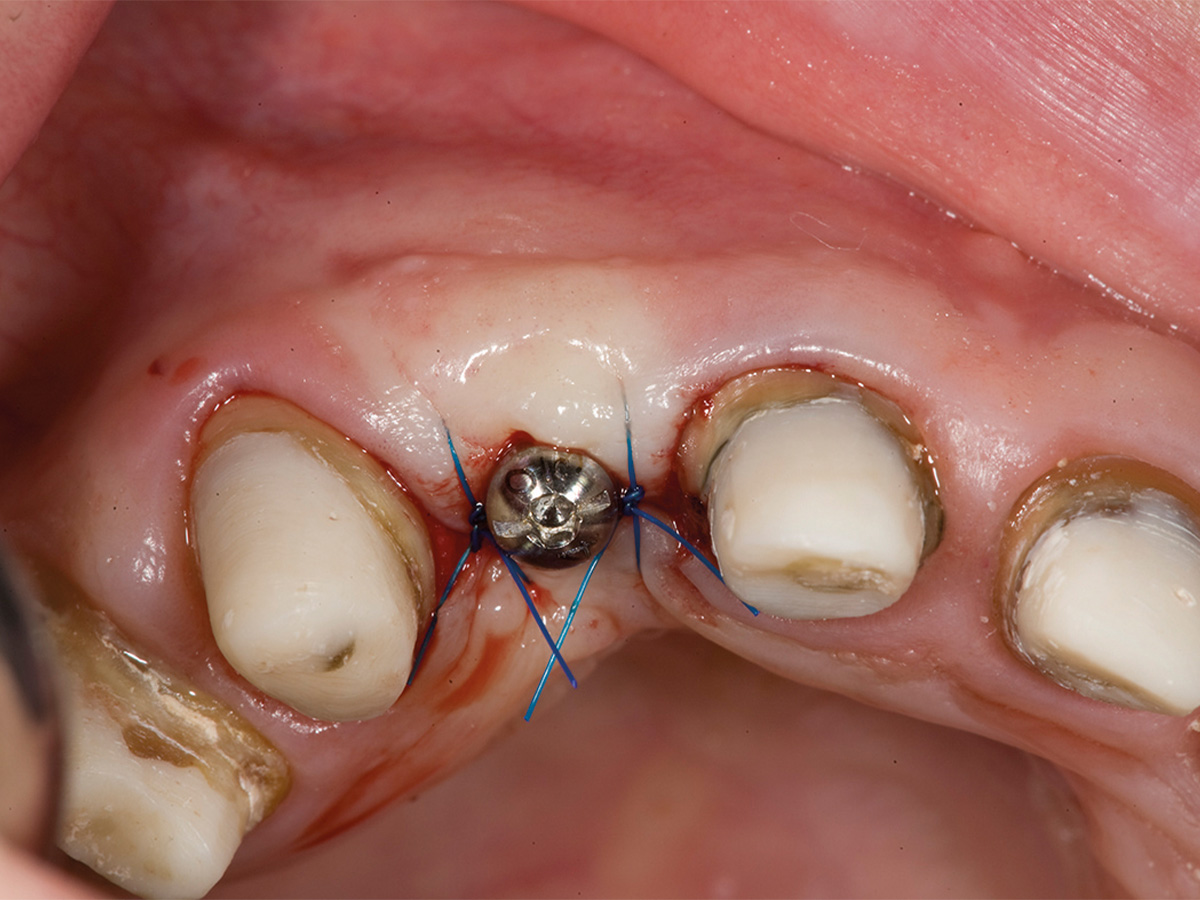

Abbildung 5a

Intraoperative Augmentation...

Abbildung 5b

nach Anfrischung des ortsständigen Knochens mit Bone Lamina/mp3...

Abbildung 5c

sowie Nagelung mit Frioss-Nägeln.